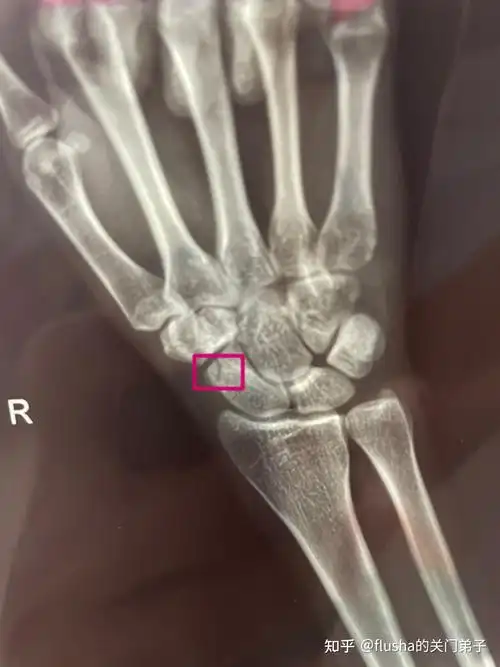

右手手腕舟骨骨折恢复过程